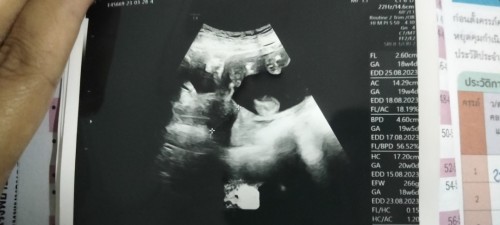

สอบถามแม่ๆหน่อยค่ะ พอดีหมอบอกว่าน้องนอนคว่ำหน้า แร้วหมอบอกว่าน้องน่าจะเป็นผู้หญิง เพราะตรงข้างล่างเป็นแบนๆ ไม่มีอะไรโผล่ออกมา อยากทราบว่าจะฟันธงได้ไหมค่ะ ว่าน้องเป็นผู้หญิงจริงๆ ตอนนี้น้องได้20สัปดาห์ กับอีก4วันแร้วค่ะ #ขอบคุณล่วงหน้านะคะ